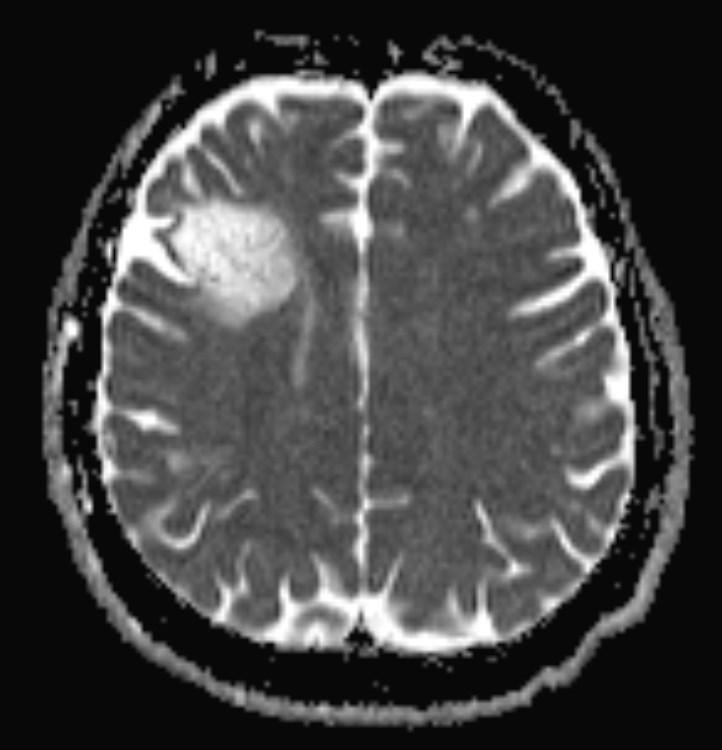

Answer: Primary hydatid cyst of right frontal lobe.

MR images revealed Gharbi type V hydatid cysts in right frontal lobe.

Gharbi classified hydatid cyst ultrasonographic images into 5 types: Type 1, walled, unilocular, anechoic; type 2, separated membranes; type 3, multisepta, daughter vesicles; type 4, heterogenic, hypo-hyperechogenic; type 5, calcification of a section of the wall or completely calcified (4). The cysts characteristically have three components: Pericyst, Exocyst, and Endocyst.